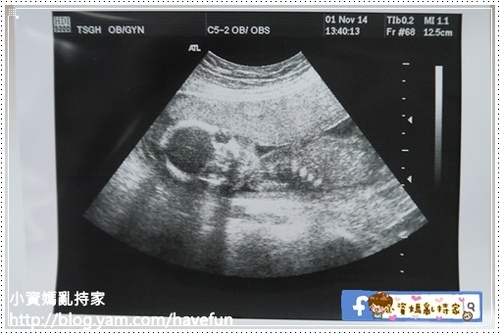

20周的超音波是政府10次產檢裡面唯一補助的一次超音波

在三總會趁這次做一個比較詳細的超音波檢查

這次也難得能夠讓我看拉拉看得久一點

看到他一會吸拇指,一會咬手指裝性感,一下又枕手睡覺,花招好多

這次的超音波除了檢查頭圍腹圍之外,也檢查了胃、肺、腎臟、膀胱等器官

感覺有點像高層次超音波的檢查項目,但是詳細程度不如高層次

其中好幾度超音波師陷入靜默,不斷的在拉拉頭頂掃來掃去

原本我很擔心是否有甚麼問題,原來是因為胎盤擋住了,超音波師看不清楚拉拉的小腦跟側腦

但超音波師還是非常有耐心的花了十幾分鐘慢慢地掃,中間幾度手痠休息,但還是堅持幫我看到了

最後因為位置關係,嘴唇沒有照到,超音波師說沒關係可以下次再照